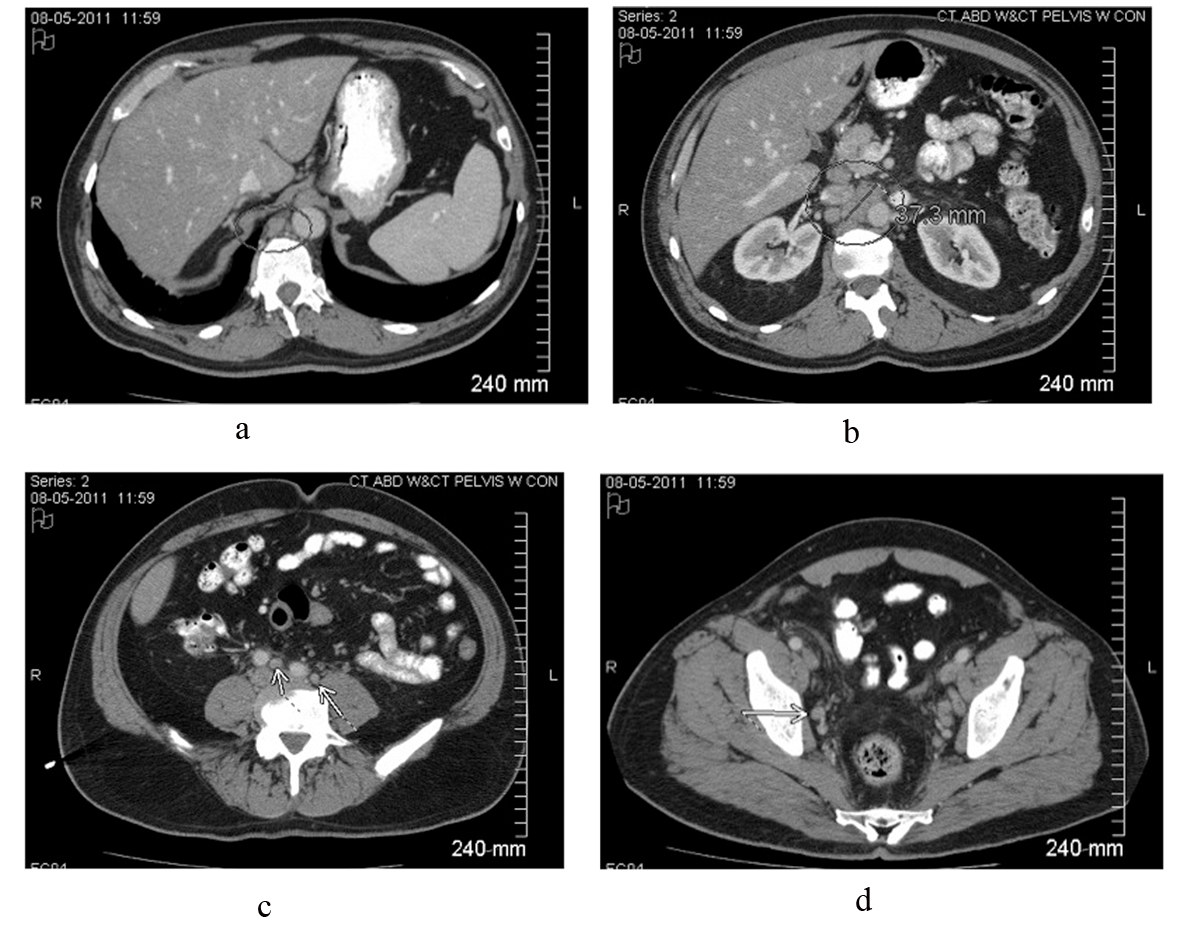

A 59-year-old white male presented to his primary care physician with 4 days of fever (about 38.3 °C), chills, mild dry cough and mild right flank discomfort without dysuria. His past medical history included gastroesophageal reflux disease and nonalcoholic steatohepatitis, and there was no family history of malignancy. Urinalysis demonstrated small leukocyte esterase and trace blood. The patient was started on a course of ciprofloxacin. Urine culture was ultimately negative, and ciprofloxacin was discontinued. Chest roentogram raised suspicion for left lower lobe infiltrate, and he was placed on azithromycin; however, daily fevers of 38.8 - 39.4 °C persisted. A CT scan of the abdomen and pelvis revealed widespread adenopathy including a confluent retroperitoneal nodal mass measuring 4 cm (Fig. 1). Biopsy was deferred pending further work-up for presumed infectious etiology.

![]() Click for large image | Figure 1. Contrast-enhanced CT scan of the abdomen and pelvis reveals intrabdominal and retroperitoneal adenopathy of uncertain origin. Adenopathy includes right retrocrural, retroperitoneal, celiac, peripancreatic, mesenteric, iliac and pelvic lymph nodes. Upper retroperitoneum reveals confluent nodal mass measuring 37.3 millimeters in image b. |